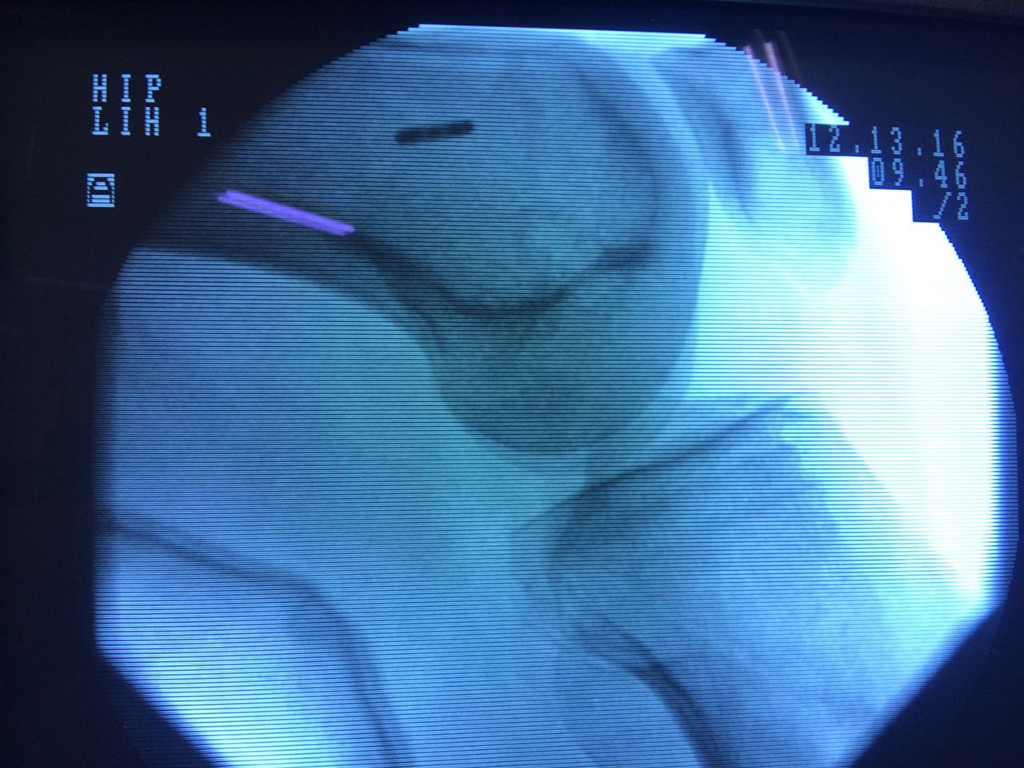

La artroscopia de rodilla es un cirugía en el cual la estructura interna de la articulación es examinada ya sea para realizar un diagnostico o para realizar un tratamiento, este procedimiento se realiza utilizando un instrumento parecido a un pequeño tubo llamado artroscopio.